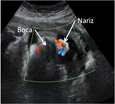

Ecografía 3D de cara y mano y torso fetales en el tercer trimestre de embarazo

La imagen ecográfica da buena cuenta de la fisonomía del bebé. Se aprecian perfectamente los rasgos principales de la cara; incluso se pueden contar los dedos de la mano que aparece en la ecografía.